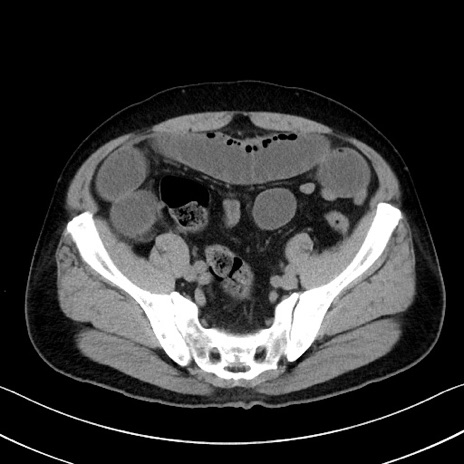

症例35(横断像)

【症例】70歳代 男性

【主訴】腹部膨満、嘔吐

【現病歴】昨日より腹部膨満感出現。本日増悪し、仙痛出現。嘔吐あり、受診。

【既往歴】糖尿病、胆摘後

【身体所見】BP 149/80mmHg、HR 74/min、BT 35.9℃、腹部:膨満、軟、圧痛なし。腸雑音減弱あり。上腹部正中切開瘢痕あり。

【データ】WBC 13500、CRP 1.72